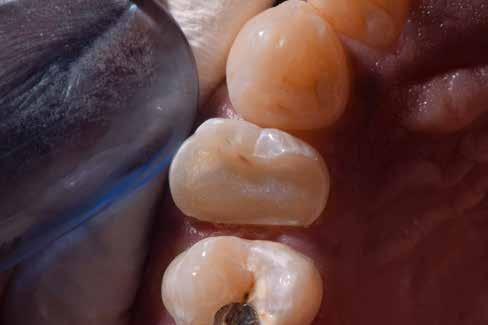

Ebben a cikkben egy 16 éves lánypáciens esetét szeretném bemutatni (1–7. képek)

A Pitts21-es fix készülékes kezelés során a harapásemelőket a felső nagyőrlő fogakra ragasztottuk, hogy a felső molárisok intrúziójával segítsék a harapás zárását (8. kép) Ún. keresztharapásos, majd később normál class 2-es gumihúzással (9–10. képek), továbbá az elülső fogakon alkalmazott ún. Rainbow harapás-záró gumihúzással (11. kép) korrigáltuk a jobb oldali teljes premolárisnyi distal-harapást, valamint az elülső nyitott harapást.

A fix fogszabályozó készülék mindössze 16 hónapos kezelés után került eltávolításra! Páciensünk legnagyobb örömére állcsontműtét nélkül sikerült mind az arcesztétikai, mind a funkcionális rehabilitáció (13–18. képek)